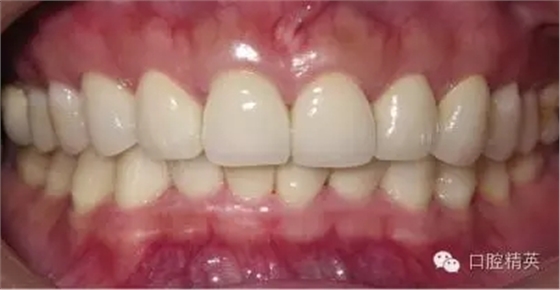

關(guān)于基礎(chǔ)治療。牙周治療和根管治療是美觀修復(fù)的基礎(chǔ)。根據(jù)術(shù)前檢查,常規(guī)先行全口潔治,必要時(shí)局部深層次的牙周治療,待牙周情況穩(wěn)定后,再考慮牙體預(yù)備與取模(見(jiàn)圖1、2)。在牙周炎未控制或牙齦紅腫的情況下,是不可能預(yù)備好牙齒,不可能取得清晰的印模,更談不上成功的美觀修復(fù)。

LAVA 全瓷冠強(qiáng)度高,顏色自然,邊緣高度密合,切端可見(jiàn)半透明感,整體效果理想,與修復(fù)前(見(jiàn)圖1)相比取得了醫(yī)患均滿意的效果。